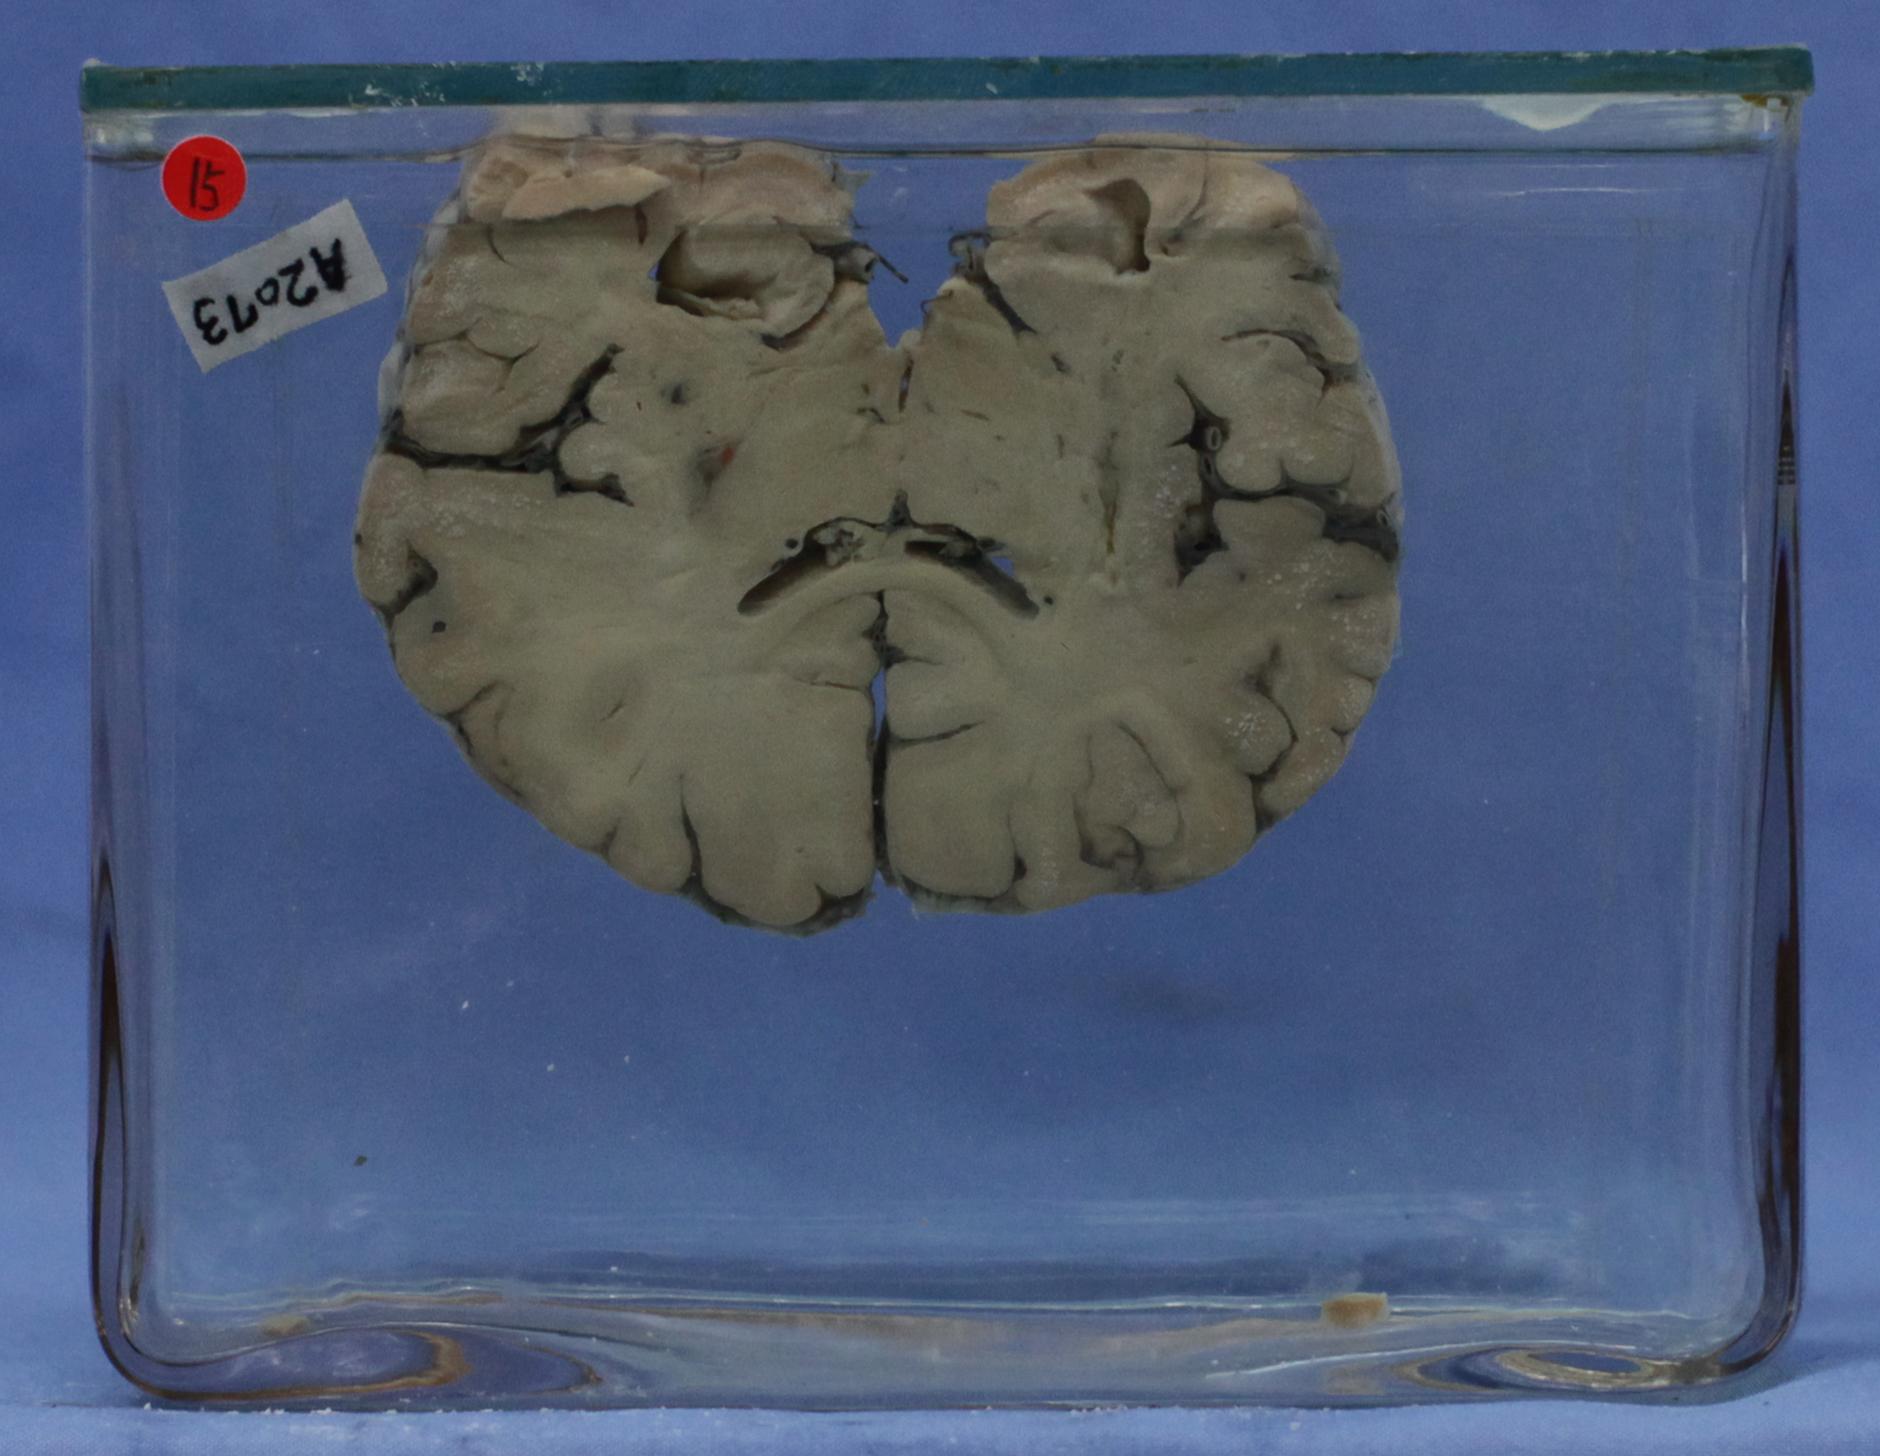

神经疾病-59-15. 双侧丘脑腔隙性出血伴梗死

经丘脑大脚冠状切面见双侧丘脑外侧各有腔隙状坏死一枚,其中尚可见含铁血黄素。